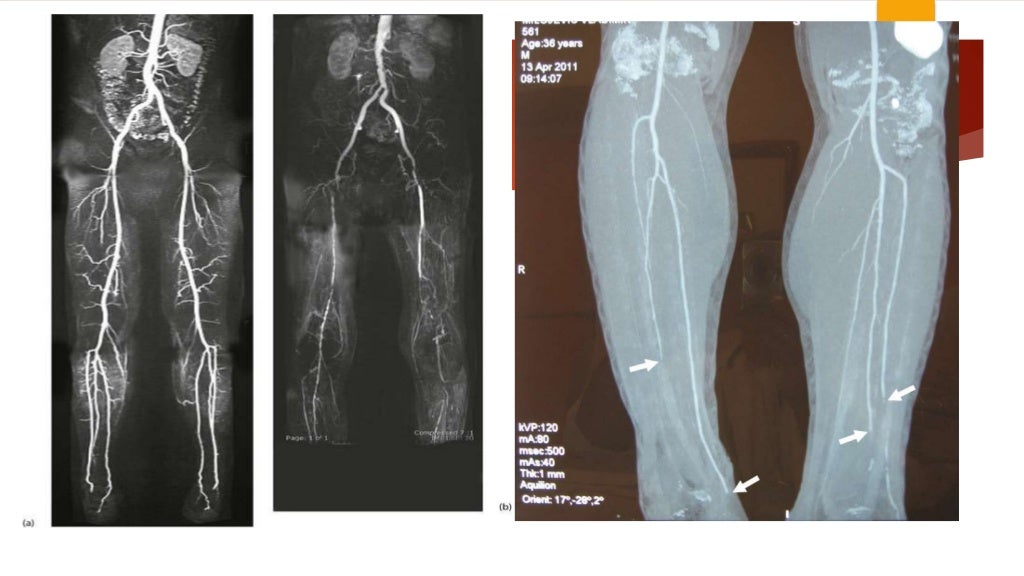

a Angiographyof the case showing typical Buerger disease. b Venous Buerger's Disease Legs Buerger’s disease is a condition where blood vessels in your arms and legs become inflamed and blocked with clots, leading to infection and gangrene. Buerger’s disease (thromboangiitis obliterans) is a rare disease of the blood vessels in your arms, legs, fingers and toes. It is typically associated with. Buerger disease causes a tightening, or a blockage, of the blood vessels. Buerger's Disease Legs.